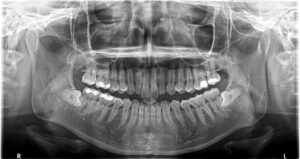

レントゲンを撮ると、左右親知らずが真横に埋まっています。

一般的にはこのような親知らずは大きな病院の口腔外科で行いますが、当院ではこのような親知らずにも対応しております。